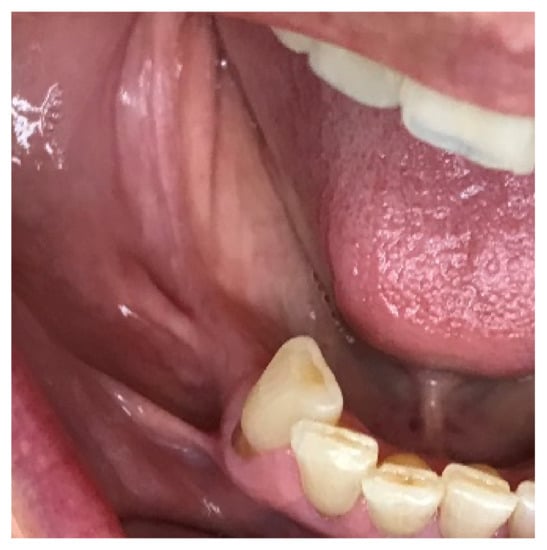

The 66-year-old patient was a healthy non-smoking female patient who lost her right mandibular molars for a long time. Previous implant placement was not successful, and an implant failure was present due to an implant fracture. Due to the risk of damaging the mandibular nerve, the broken implant was left in the jaw (as a “sleeping” implant), covered completely by the bone. That implant was left in the jaw, which presented a severe atrophy, with a remaining residual bone height of approximately 4 mm. Based on the height, the placement of short implants was not an option, and the patient was informed about the different grafting options, as well as the possible intraoperative and postoperative complications (Figure 1).

Figure 1.

Clinical situation: bone deficiency in the right posterior mandible.